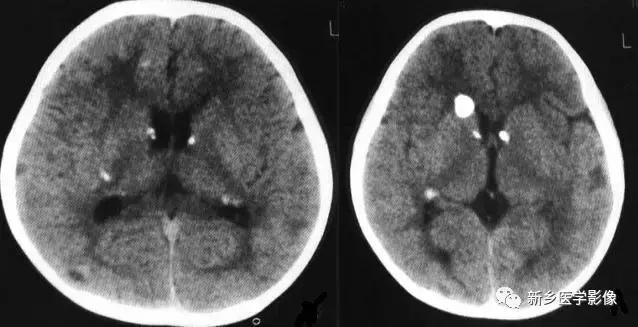

结核性脑膜炎患者后期,约半数在靠近颅底部、鞍区附近出现散在钙化斑点,区别于其他细菌性脑膜炎。

脑内结核瘤早期,中线干酪样坏死区可出现斑点状钙化,增强扫描时周围呈环状强化,与病灶中心点状高密度钙化,构成典型的结核瘤的“靶样征”,是识别结核瘤的重要证据;

晚期,整个结核瘤可出现钙化,呈结节状,也可仅其壁部分出现钙化,呈断续之环状或蛋壳状。